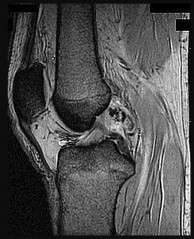

Question 5:

When performing an anterior cruciate ligament (ACL) reconstruction using a bone-patellar tendon-bone autograft, placement of the femoral tunnel too anteriorly (shallow) will most likely result in:

Correct Answer: Increased laxity in extension and tightness in flexion

Explanation:

If the femoral tunnel is placed too anteriorly, the graft will be tight in flexion and loose in extension. Conversely, if it is placed too posteriorly (deep), it will be tight in extension and loose in flexion.